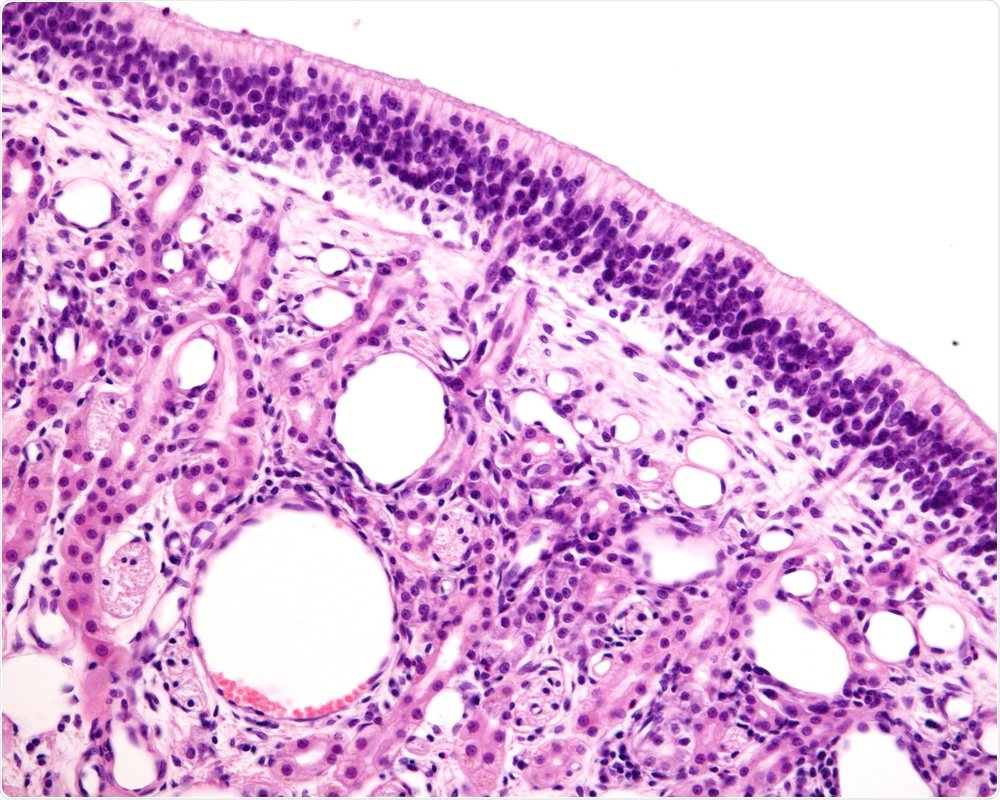

In these cases, if you carry out microscopic studies of the tissue, you can see that the virus has damaged the structure of the receptor cells.

Typically, you will see that the fine hair endings that dangle down into the mucus have dropped away, therefore the cells cannot pick up any smells from the nasal mucus.

Olfactory Mucosa

Image Credit: Jose Luis Calvo/Shutterstock.com